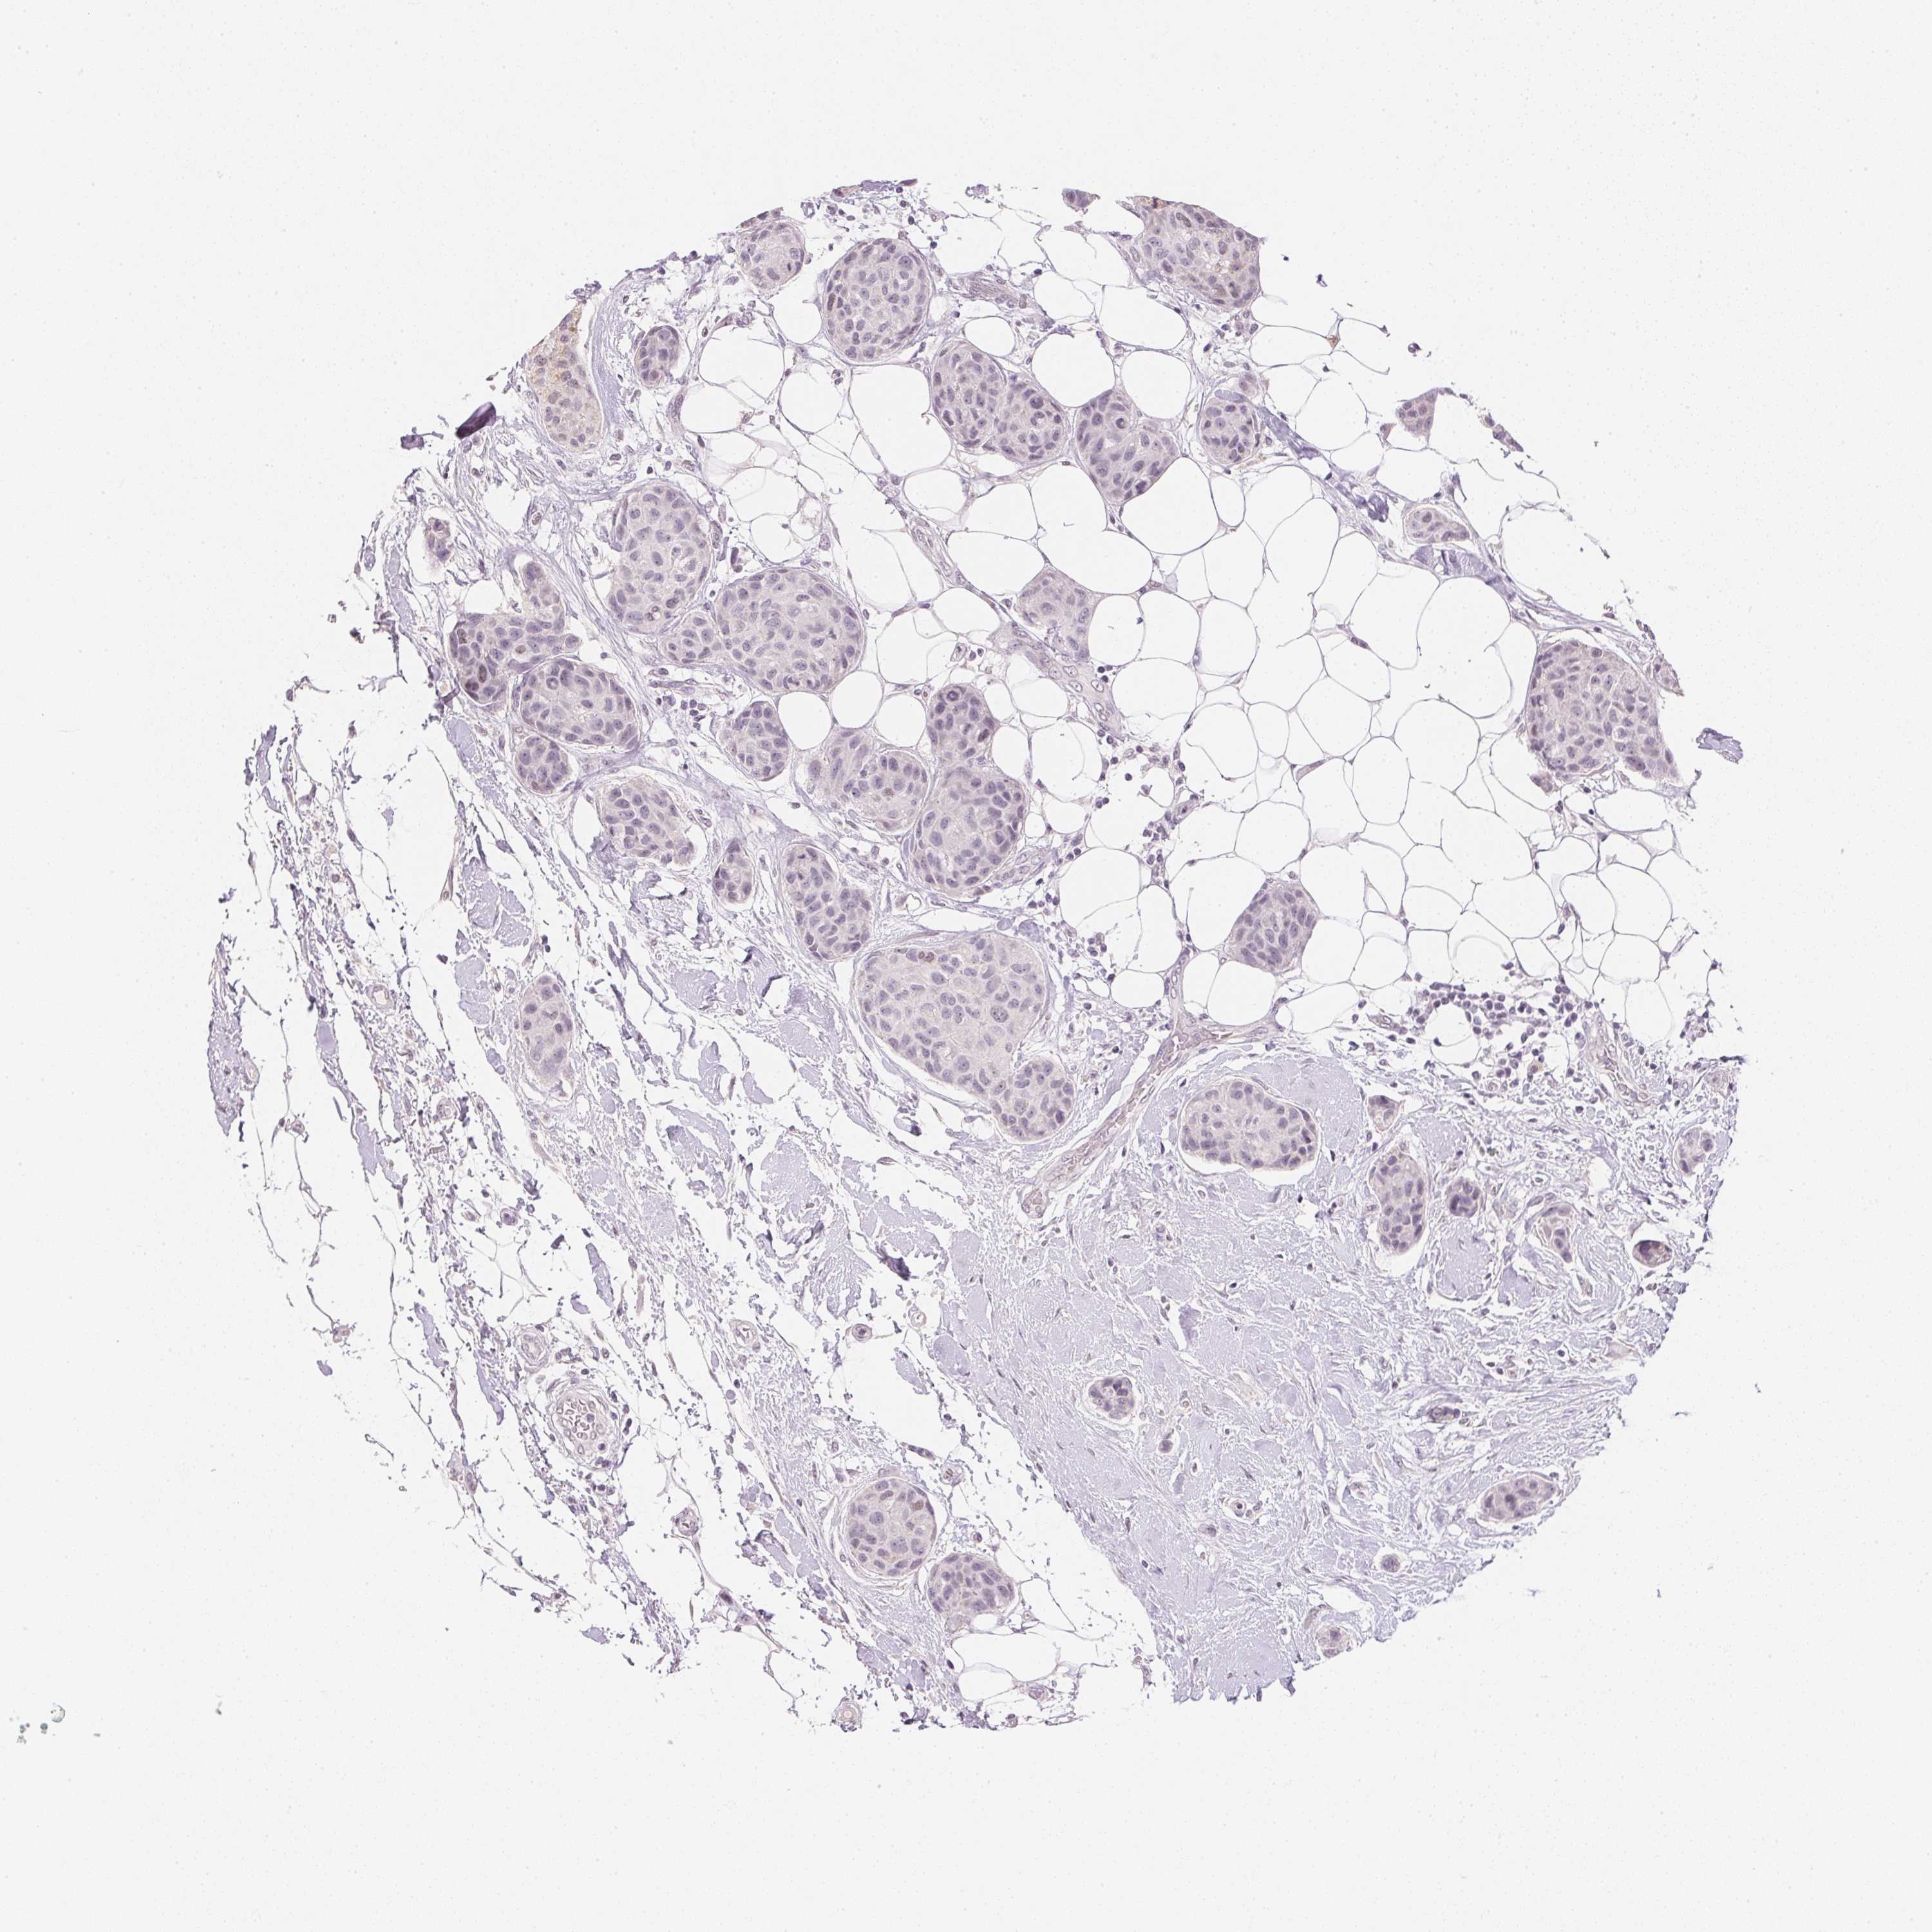

CANCER BREAST CANCER Show tissue menu

BRCA TCGA BRCA VALIDATION PROTEIN EXPRESSION